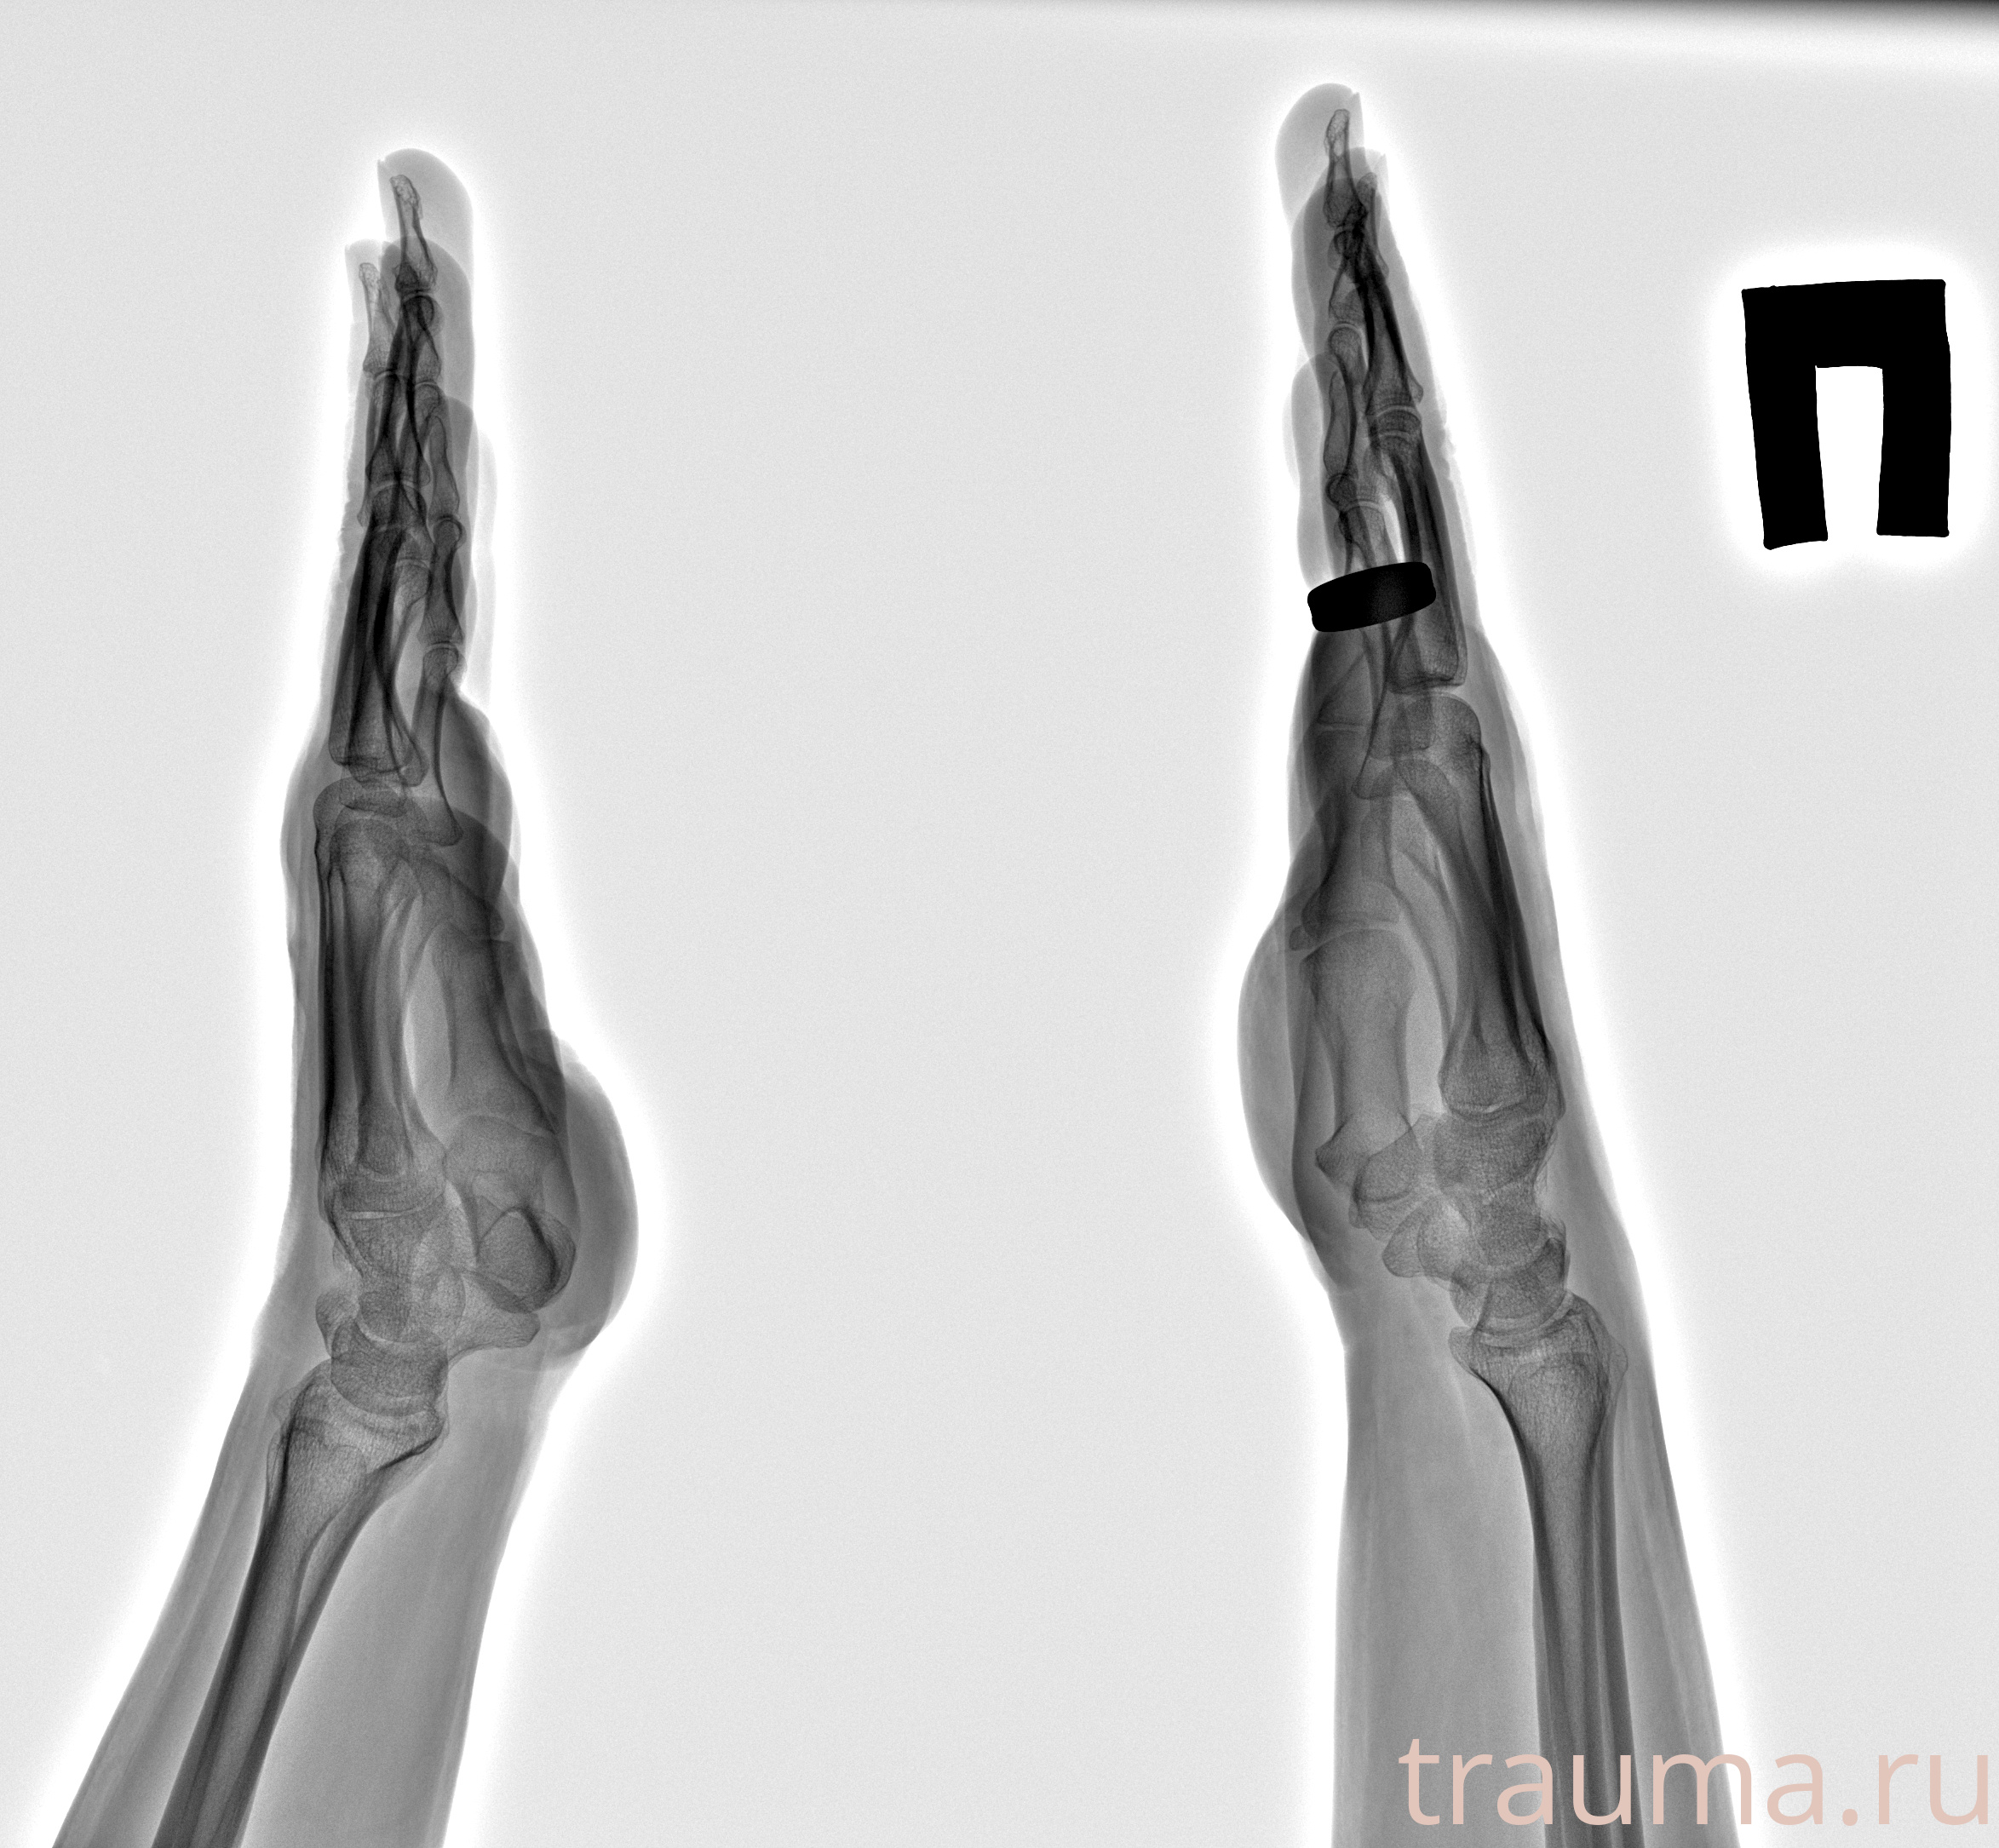

Рентгенограммы

Рентген на дому: по вашему адресу приезжает врач-рентгенолог, травматолог-ортопед с мобильным рентгеновским аппаратом, проводит диагностику травмы или заболевания, делает необходимые рентгенограммы, дает рекомендации по дальнейшему лечению. Получить качественные снимки в домашних условиях возможно благодаря уникальной методике, разработанной МосРентген Центром для института  Склифосовского